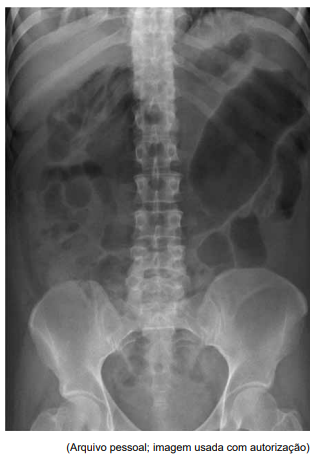

Homem de 32 anos, portador de retocolite ulcerativa há

5 anos, em uso irregular de mesalazina, procura o pronto-socorro por dor abdominal difusa e intensa há 24 horas, acompanhada de distensão abdominal progressiva e febre (38,9 ºC), além de diarreia sanguinolenta há

5 dias. Ao exame físico, apresenta abdome distendido,

timpânico, difusamente doloroso e ruídos hidroaéreos diminuídos. A frequência cardíaca é de 124 bpm e a pressão arterial de 90 x 60 mmHg. Os exames laboratoriais

relevantes para o caso são: leucócitos: 18.500/mm3

;

hemoglobina: 10,2 g/dL; PCR: 160 mg/L; e creatinina:

1,9 mg/dL. A radiografia simples do abdome é demonstrada na imagem a seguir:

Foram iniciados jejum, hidratação, antibioticoterapia e corticoterapia, porém sem melhora dos parâmetros clínicos nas primeiras 24 horas. Dessa forma, a conduta indicada neste momento é: